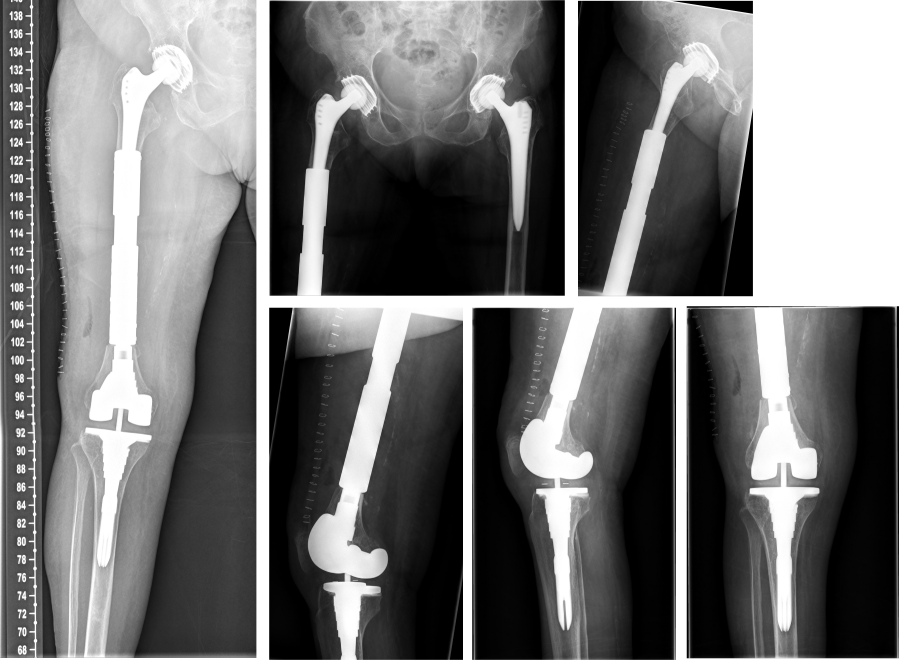

The surgical procedure for subtotal replacement of the femoral diaphysis was performed without any intra- or postoperative complication. The duration for the surgical intervention was one hour and 40 minutes. The patient was then mobilized with full weight bearing supervised by physiotherapists at ward level, which she tolerated well. The pain was significantly relieved during hospital stay. The postoperative radiographs showed correct implant position and a satisfactory surgical result (Figure 6 [Fig. 6]).

Figure 6: The postoperative radiographs showed correct implant.

At one-year follow-up, the patient did not complain of any pain. The Harris Hip Score HHS improved from 26 (prior to partial diaphyseal replacement) to 83 at one-year follow-up (Figure 7 [Fig. 7]), the Western Ontario and McMaster Universities Osteoarthritis Index WOMAC improved from 88 to 16. The range of motion of the right hip joint one year after surgery was: extension/flexion 0/0/90°, abduction/adduction 30/0/20°, external rotation/internal rotation 30/0/20°. The range of motion of the right knee joint one year after surgery was: extension/flexion: 0/0/120°. There were no symptoms or signs of infection or any other complications.

Figure 7: Postoperative radiographs one year after surgery without any morphological changes compared to postoperative radiographs